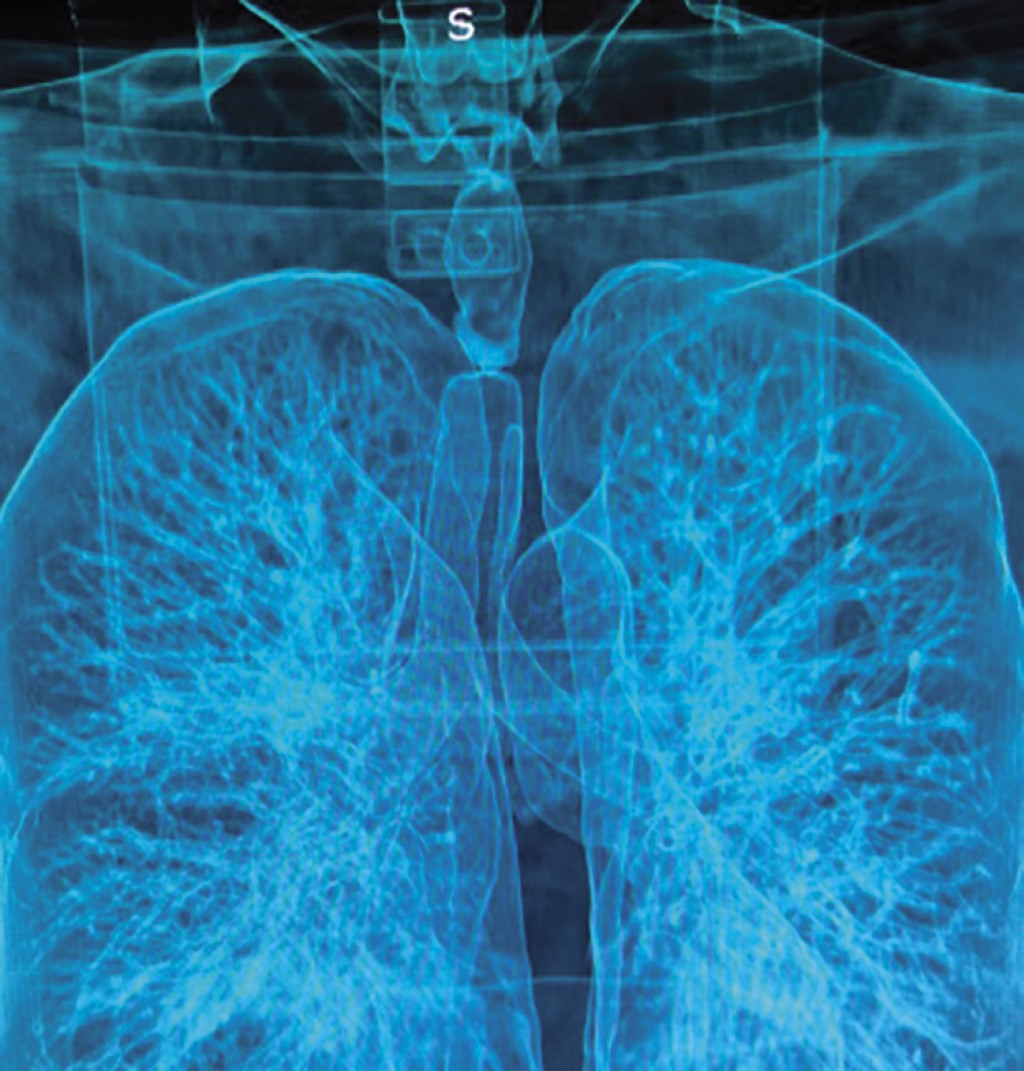

Tracheal resection and anastomosis, continuous versus separated stitches: an experience of 15 years

Acuña-Pinzón, Camilo Levi1,3; Martínez-Zamorano, Monserrat1,4; Acuña-Pinzón, Alan Felipe2,5; Condoy-Nieves, Jefferson Fabián1,6; Narváez-Fernández, Salvador1,7